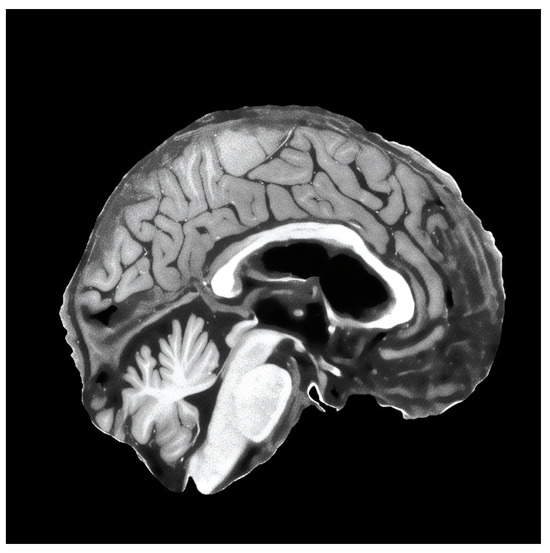

For the validation of the methodology in the detection of the MCI task, we used ADNI (Alzheimer’s Disease Neuroimaging Initiative) [50] and the Open Access Series of Imaging Studies (OASIS) v4 [74] datasets. We combined both datasets to have a broader spectrum of images in our training and validation sets, and we prepared three datasets out of the combined full dataset. Initially, all datasets were preprocessed with our suggested MRI preprocessing pipeline [25], which included spatial normalization, intensity normalization, and skull stripping. Then, we extracted mid slices (sagittal, coronal and axial) of the brain from each patient, which were resized to 256 × 256 resolution. Dataset descriptions are given below:

• Additional to augmentations, before applying augmentation, it super-resolves the preprocessed slices to 1024 × 1024 resolution with the improved super-resolution method. An example of a super-resolved image is depicted in Figure 3.